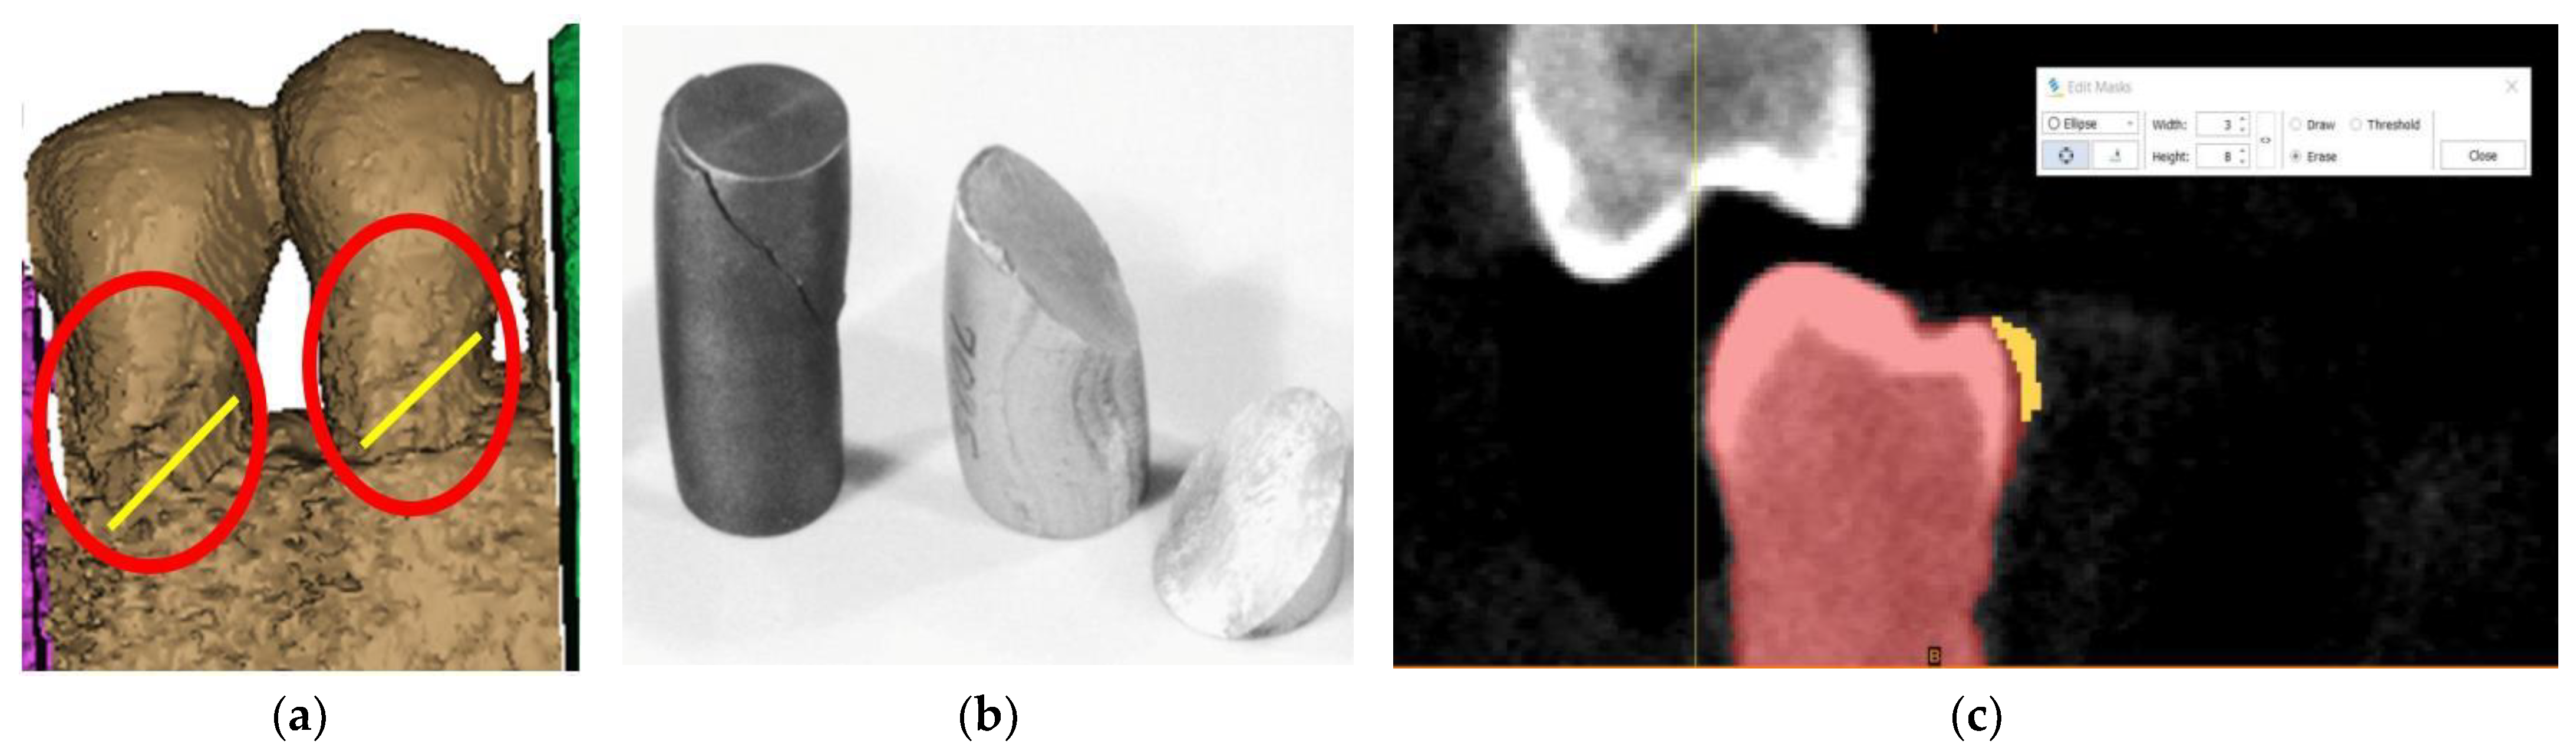

2. Case Description

3. Finite Element Analysis (FEA) of Mandibular Right Premolars